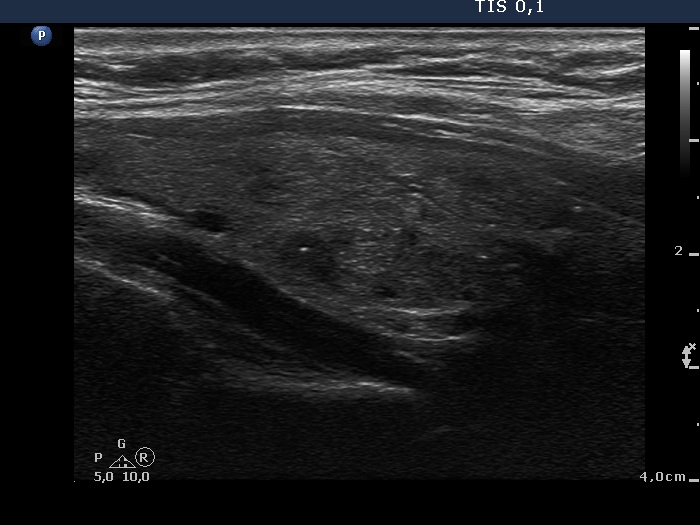

Parathyroid lesions - case 907 (ultrasonographic picture 13)

Left lobe, another longitudinal scan.